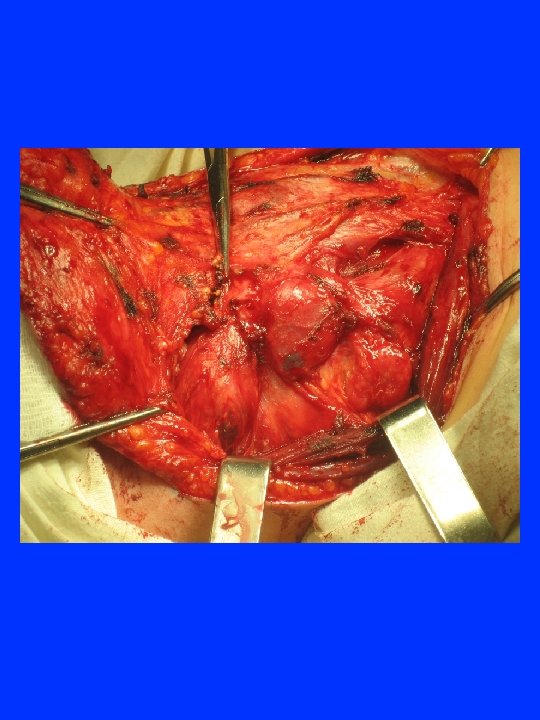

ЛАРИНГО-ТРАХЕАЛЬНАЯ ИНВАЗИЯ 33. 1% 17. 0% 9. 9% 4 - 20 21 - 40 41 - 60 61 - 84 возраст

ЛАРИНГО – ТРАХЕАЛЬНАЯ ИНВАЗИЯ РАКА ЩИТОВИДНОЙ ЖЕЛЕЗЫ